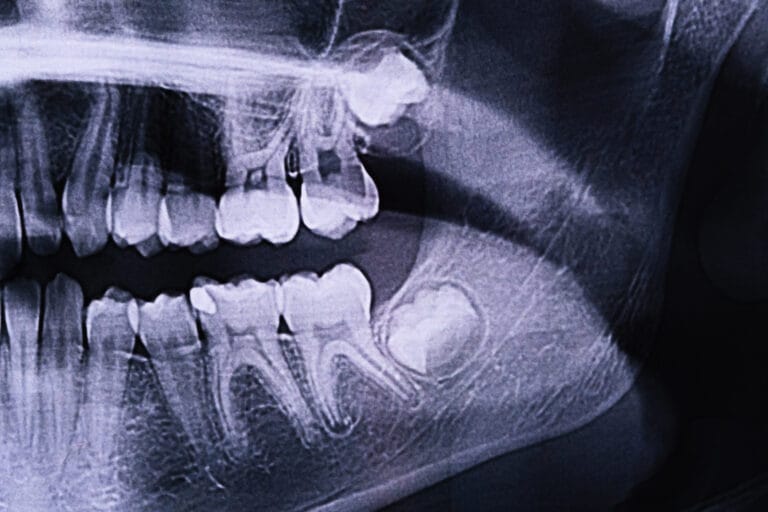

Wisdom teeth are often no longer needed due to changes in diet and advances in dental care. Over time, human jaws have become smaller because we don’t need as much chewing power. This evolutionary change means that there is often not enough room in the mouth for wisdom teeth to come in properly. North Tarrant OMS explains that as our diets became softer and cooking techniques improved, the need for extra chewing power diminished, leading to smaller jaws.

Additionally, the benefits of dental hygiene, such as regular brushing and flossing, have reduced tooth decay and loss, which were more common in our ancestors. As a result, the space once required for wisdom teeth has shrunk, and these teeth often become impacted or misaligned when they try to emerge.

Dentists often recommend removing wisdom teeth to prevent potential problems. Since many people’s mouths do not have enough space for these teeth, they can become impacted, meaning they are trapped beneath the gums and unable to emerge properly. Impacted wisdom teeth can cause pain, infection, and damage to adjacent teeth. WebMD notes that impacted wisdom teeth can lead to cysts, which can damage the jawbone and nerves.

Impacted wisdom teeth can cause pain, infection, and damage to other teeth. They can also lead to overcrowding, making it difficult to maintain proper oral hygiene. According to NCBI, untreated wisdom teeth can result in cavities, gum disease, and cysts. If these problems occur, you may end up needing more extensive dental work in the future.